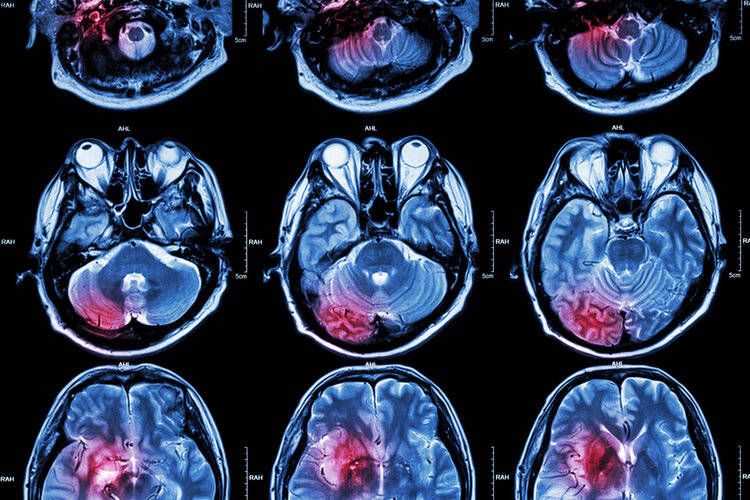

看病5分钟 , 检查一整天 。 不少患者对于这种流程都表示不解 。 今天小艾就和大家絮叨一下 , 为什么看病要做这么多检查 。

以磁共振为例 , 不同品牌的仪器清晰度、个别序列的信号值等方面存在一定差别 , 出来的结果也会存在差异 。 对于局部精细解剖结构的科室 , 临床医生也习惯用本院的片子读片 。 此外 , 要求多层扫描的检查 , 检查下来有几百个平面 , 而实际打印只有几十张 , 中间很可能出现细节丢失 。